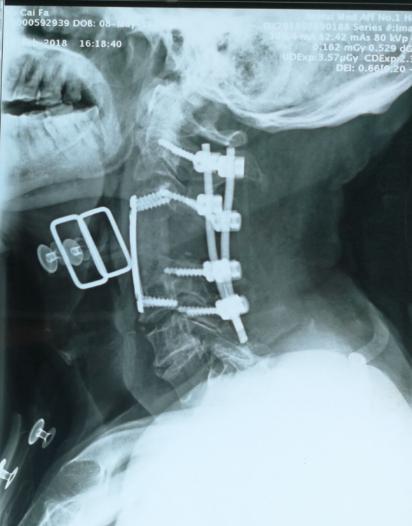

骨病骨肿瘤科近日完成 “颈4单椎体肿瘤伴病理性骨折行颈4全脊椎切除手术 ”1例。患者70岁男性,双肩部不适右上肢无力1月余,经检查提示颈4椎体单椎体肿瘤,颈椎椎体生理结构复查,涉及生命中枢脊髓和脑供血动脉椎动脉,该部位手术类似刀尖上跳舞,一不小心可导致患者的终身瘫痪或生命终结。 胡勇教授团队根据患者病情,制定精细手术方案,多套手术预案,采用颈椎前后联合入路实施颈4全脊椎切除+颈椎重建手术,术中既完整的切除了肿瘤,又精细地完成对脊髓和椎动脉的有效保护。术后5天患者即可在支具保护下起床活动并顺利康复出院,无伤口及神经并发症发生。胡勇教授指出:脊椎肿瘤的治疗需针对每个患者制定个性化治疗方案。颈椎邻近解剖结构复杂,肿瘤常常与椎动脉等血管、神经粘连,手术风险高、难度大,以往手术目的大多停留在提供组织学诊断、神经减压、减轻疼痛,而手术切除通常采用颈椎病或外伤的椎体次全切除或次全椎节切除的模式,显然难以达到肿瘤病灶彻底切除的目的。全脊椎切除+脊柱重建手术越来越多地被应用于脊柱原发恶性肿瘤和孤立性转移肿瘤,全脊椎切除能显著降低脊椎原发性骨肿瘤局部复发率,改善脊髓神经功能, 可以减少术中出血和肿瘤细胞残留,提高患者治愈率和生存率。

全脊椎切除手术是国家级区域医疗中心要求核心技术手术,该手术的顺利实施,标志我科在脊柱肿瘤的治疗上又向国内更高、更精、更尖水平迈进了一大步。(胡博/徐生林)